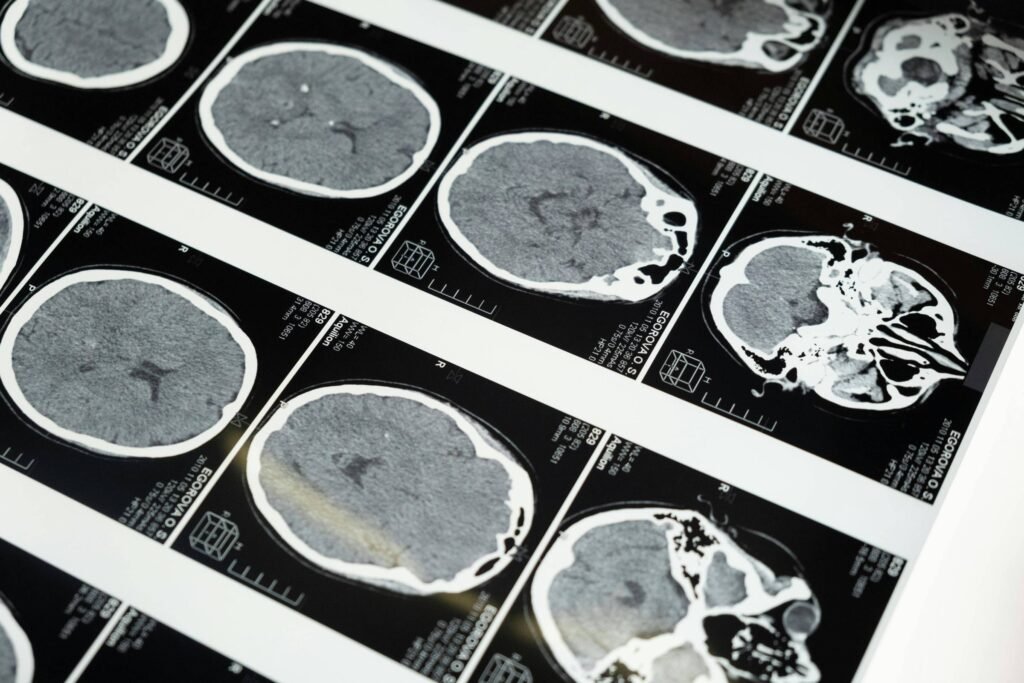

Desde os anos 1990, é sabido que a doença de Alzheimer se desenvolve pela presença da proteína amiloide ou beta-amiloide no cérebro, segundo Caramelli. “Então o que se acredita é que ao remover essa amiloide aconteça uma modificação na progressão da doença ao longo do tempo”, diz.

E é assim que donanemabe funciona. Na doença de Alzheimer, aglomerados de proteína beta-amiloide formam placas no cérebro e o medicamento atua ligando-se a esses aglomerados e reduzindo-os, prometendo um retardamento da progressão da doença.